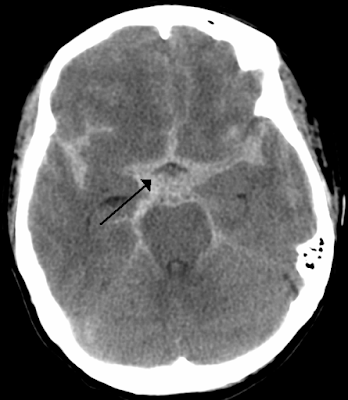

PART 3: Aneurysmal subarachnoid hemorrhage

What should your blood pressure goals be in acute aneurysmal SAH awaiting definitive care?

Goal is to prevent rebleeding. The risk of rebleeding is maximal in the first 12 hours, Recurrence rates between 4% and 13.6% within the first 24 hours.

Most of the data for the systolic target comes from a Japanese study done by Okhuma et al in 2001. They reviewed 273 cases of SAH which were transferred to their center for definitive treatment. Of the 273 patients, 37 had rebleeding. They then compared the rebleed group to the non-rebleed group to see which patient variables were associated with rebleeding.

The mean value of systolic arterial blood pressure in the rebleed group, which was measured within 20 minutes before rebleeding, was 172 mmHg. The mean value of the maximum value of sBP in the non-rebleed group was 153 mmHg which was statistically significantly.

They also looked at the distribution of the values of systolic blood pressure in the rebleed group and in the non-rebleed group were compared at various cutoff points. For BP above 160 the OR was 3.1 of rebleed.

Their conclusion was that systolic BP over 160 was associated with increased risk of rebleeding.

There are no RCTs looking at this so in the meantime we are forced to use this limited observational study as our guide.